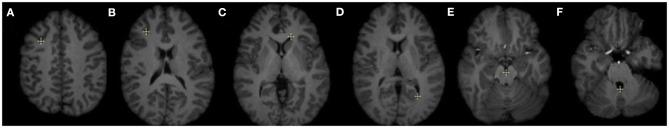

In image-guided neurosurgery, co-registered preoperative anatomical, functional, and diffusion tensor imaging can be used to facilitate a safe resection of brain tumors in eloquent areas of the brain. However, the brain deforms during surgery, particularly in the presence of tumor resection. Non-Rigid Registration (NRR) of the preoperative image data can be used to create a registered image that captures the deformation in the intraoperative image while maintaining the quality of the preoperative image. Using clinical data, this paper reports the results of a comparison of the accuracy and performance among several non-rigid registration methods for handling brain deformation. A new adaptive method that automatically removes mesh elements in the area of the resected tumor, thereby handling deformation in the presence of resection is presented. To improve the user experience, we also present a new way of using mixed reality with ultrasound, MRI, and CT. This study focuses on 30 glioma surgeries performed at two different hospitals, many of which involved the resection of significant tumor volumes. An Adaptive Physics-Based Non-Rigid Registration method (A-PBNRR) registers preoperative and intraoperative MRI for each patient. The results are compared with three other readily available registration methods: a rigid registration implemented in 3D Slicer v4.4.0; a B-Spline non-rigid registration implemented in 3D Slicer v4.4.0; and PBNRR implemented in ITKv4.7.0, upon which A-PBNRR was based. Three measures were employed to facilitate a comprehensive evaluation of the registration accuracy: (i) visual assessment, (ii) a Hausdorff Distance-based metric, and (iii) a landmark-based approach using anatomical points identified by a neurosurgeon. The A-PBNRR using multi-tissue mesh adaptation improved the accuracy of deformable registration by more than five times compared to rigid and traditional physics based non-rigid registration, and four times compared to B-Spline interpolation methods which are part of ITK and 3D Slicer. Performance analysis showed that A-PBNRR could be applied, on average, in <2 min, achieving desirable speed for use in a clinical setting. The A-PBNRR method performed significantly better than other readily available registration methods at modeling deformation in the presence of resection. Both the registration accuracy and performance proved sufficient to be of clinical value in the operating room. A-PBNRR, coupled with the mixed reality system, presents a powerful and affordable solution compared to current neuronavigation systems.

在图像引导的神经外科手术中,术前共配准的解剖、功能和扩散张量成像可用于促进在脑功能区安全切除脑肿瘤。然而,手术过程中大脑会发生变形,尤其是在进行肿瘤切除时。术前图像数据的非刚性配准(NRR)可用于创建一个配准图像,该图像能捕捉术中图像的变形,同时保持术前图像的质量。本文利用临床数据报告了几种处理脑变形的非刚性配准方法在准确性和性能方面的比较结果。提出了一种新的自适应方法,该方法能自动去除切除肿瘤区域的网格元素,从而处理存在切除情况时的变形。为了改善用户体验,我们还提出了一种将混合现实与超声、MRI和CT结合使用的新方法。本研究聚焦于在两家不同医院进行的30例胶质瘤手术,其中许多手术涉及切除较大体积的肿瘤。一种基于自适应物理的非刚性配准方法(A-PBNRR)为每位患者配准术前和术中MRI。将结果与其他三种现成的配准方法进行比较:在3D Slicer v4.4.0中实现的刚性配准;在3D Slicer v4.4.0中实现的B样条非刚性配准;以及在ITKv4.7.0中实现的PBNRR(A-PBNRR基于此)。采用了三种措施来全面评估配准准确性:(i)视觉评估;(ii)基于豪斯多夫距离的度量;(iii)使用神经外科医生确定的解剖点的基于地标方法。与刚性和传统基于物理的非刚性配准相比,使用多组织网格自适应的A-PBNRR将可变形配准的准确性提高了五倍多,与作为ITK和3D Slicer一部分的B样条插值方法相比提高了四倍。性能分析表明,A-PBNRR平均可在不到2分钟内应用,达到了临床环境中使用所需的速度。在模拟存在切除情况时的变形方面,A-PBNRR方法的表现明显优于其他现成的配准方法。配准的准确性和性能都证明足以在手术室中具有临床价值。与当前的神经导航系统相比,A-PBNRR与混合现实系统相结合提供了一种强大且经济实惠的解决方案。